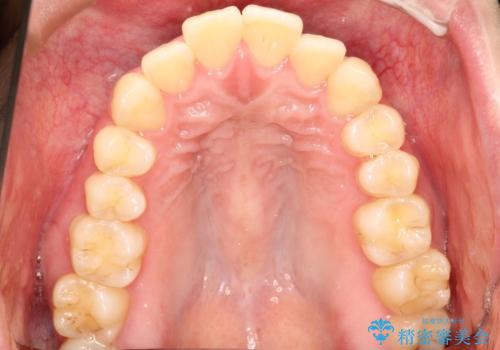

上下左右の前から4番目の歯を抜歯して、上下の前歯を後方に移動させる計画としました。